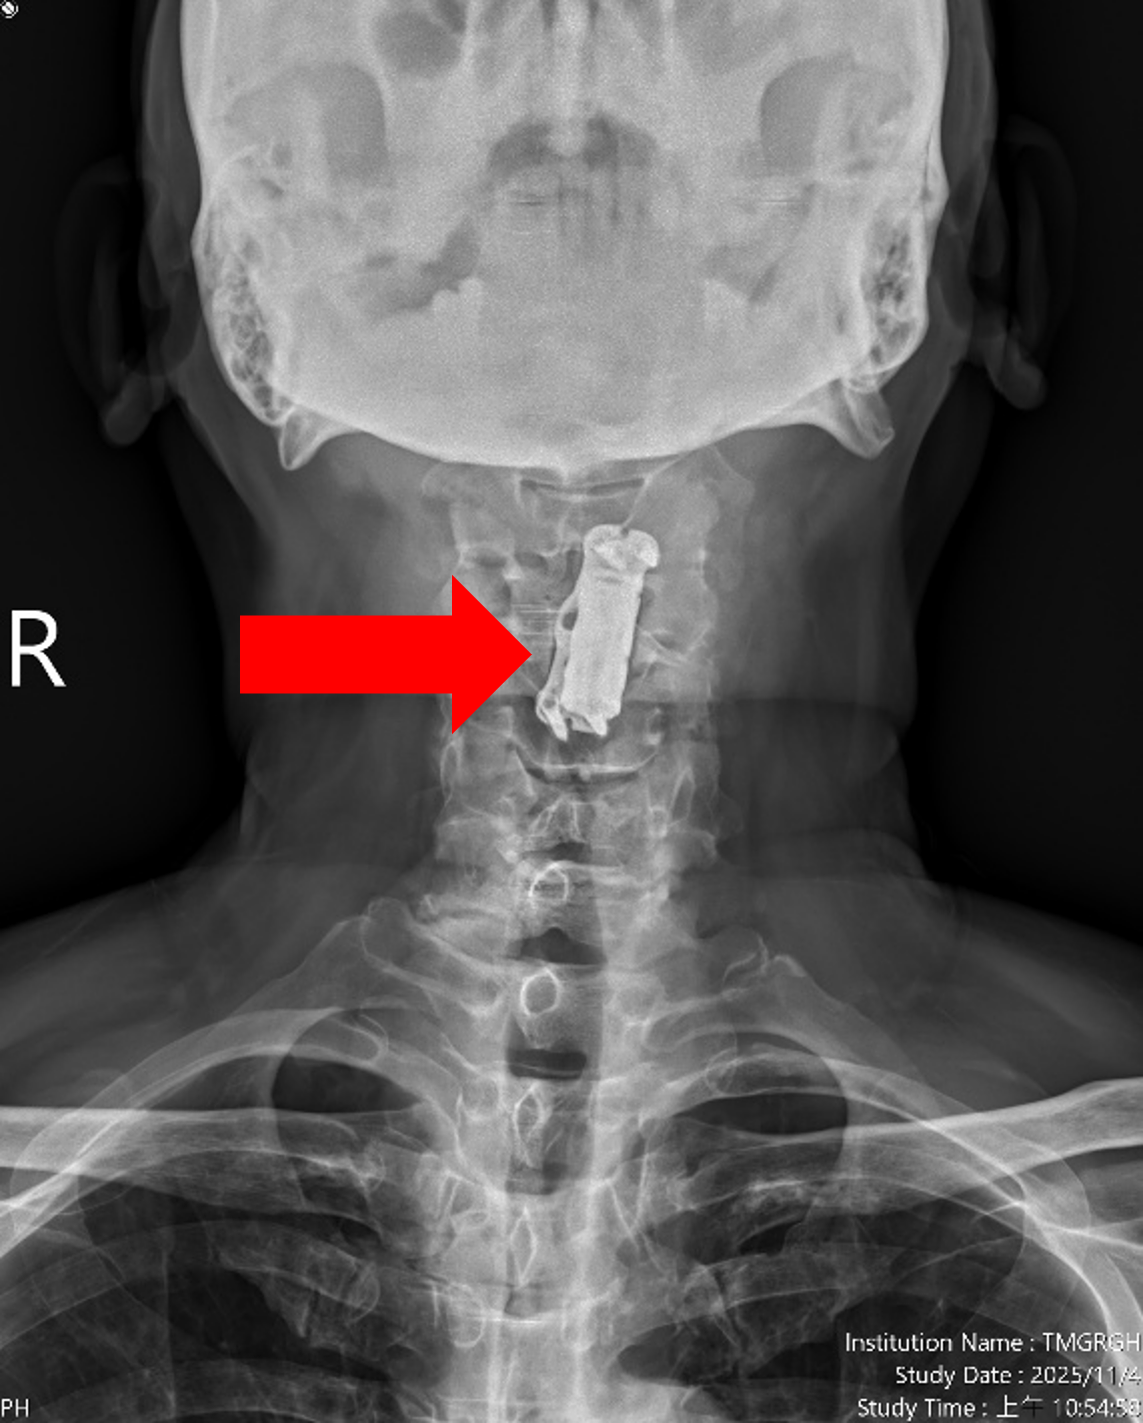

圖一、【治療前】患者曾於年初接受其他醫療院所執行第四頸椎體切除,籠狀支架融合(如左圖紅色箭頭)及第三第五頸椎骨釘骨板固定手術(如右圖藍色箭頭),並有第五第六及第六第七頸椎間盤退化及狹窄情況(如右圖綠色箭頭)。